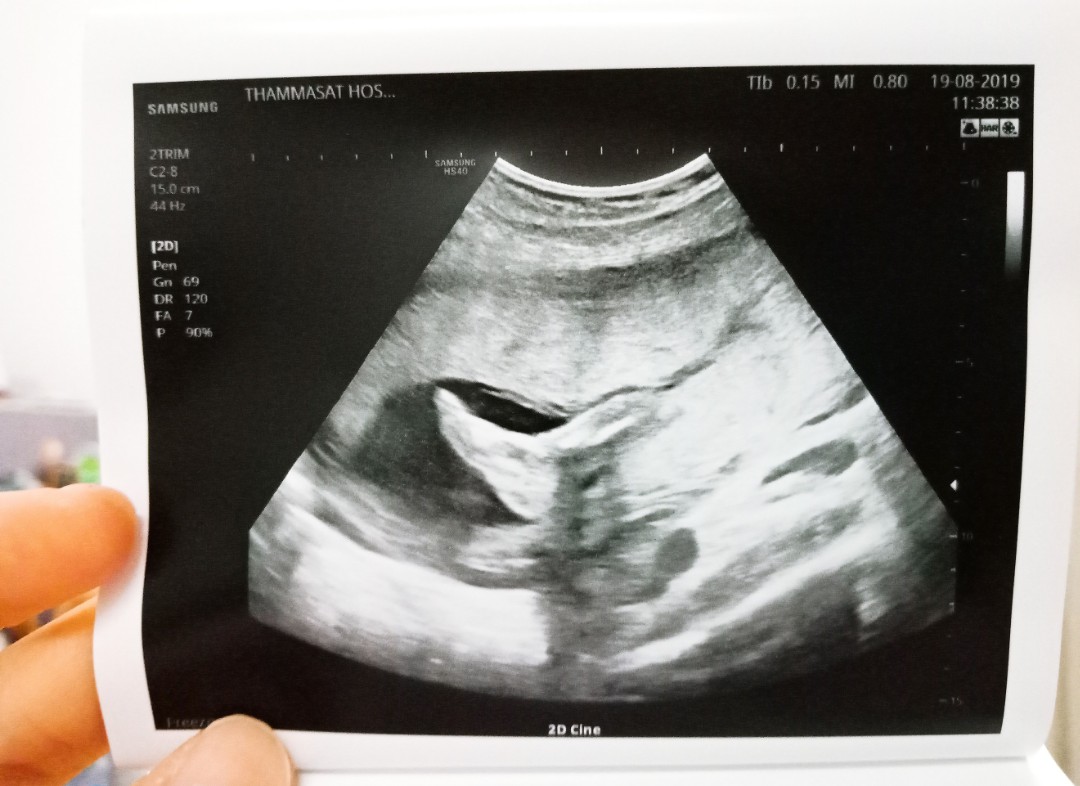

ซาวน์ตอน 19w ตอนนี้จะเข้า 21w แล้วจ้า

นี้เลยค่ะยกมาใส่หน้า5555 ตอนนั้น25w ปัจจุบัน 28wแล้วค่ะ

มาแบบนี้เลยค่ะ ซาวน์ตอน 21 w ตอนนี้24 w แล้วค่ะ